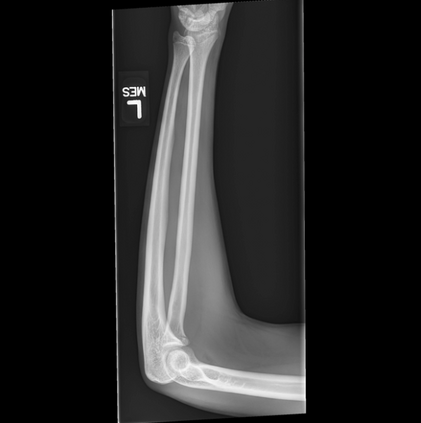

In this study, we aim to initiate the development of Radiology Foundation Model, termed as RadFM.We consider the construction of foundational models from the perspectives of data, model design, and evaluation thoroughly. Our contribution can be concluded as follows: (i), we construct a large-scale Medical Multi-modal Dataset, MedMD, consisting of 16M 2D and 3D medical scans. To the best of our knowledge, this is the first multi-modal dataset containing 3D medical scans. (ii), We propose an architecture that enables visually conditioned generative pre-training, allowing for the integration of text input interleaved with 2D or 3D medical scans to generate response for diverse radiologic tasks. The model was initially pre-trained on MedMD and subsequently domain-specific fine-tuned on RadMD, a radiologic cleaned version of MedMD, containing 3M radiologic visual-language pairs. (iii), we propose a new evaluation benchmark that comprises five tasks, aiming to comprehensively assess the capability of foundation models in handling practical clinical problems. Our experimental results confirm that RadFM significantly outperforms existing multi-modal foundation models. The codes, data, and model checkpoint will all be made publicly available to promote further research and development in the field.